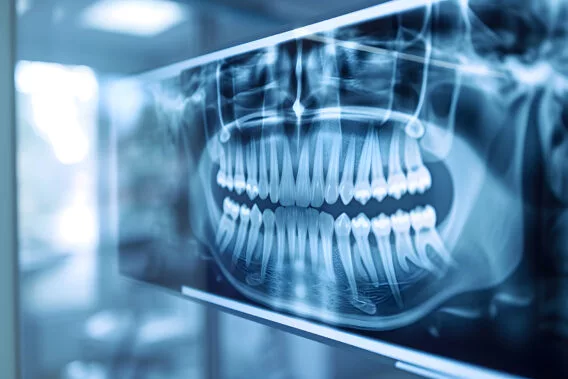

Röntgenfoto’s

Röntgenfoto’s laten zien wat met het blote oog niet zichtbaar is, zoals verborgen gaatjes, wortelproblemen of botverlies.